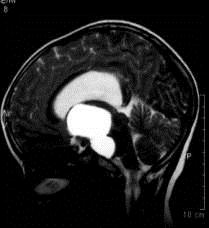

病历摘要:??患者女性,6岁,半年来感觉视力模糊,近10天出现反复头痛,间有恶心呕吐,精神转差,查体:神志清楚,身高90cm,体重25Kg,血压90/55...

问题 病历摘要:??患者女性,6岁,半年来感觉视力模糊,近10天出现反复头痛,间有恶心呕吐,精神转差,查体:神志清楚,身高90cm,体重25Kg,血压90/55mmHg,右眼视力4.6,左眼视力4.8,双侧视乳头水肿,颈软,伸舌居中,四肢肌张力正常,肌力5级,双侧Babinski征(-)。 患者术后第三天,神志逐渐转差,浅昏迷状态,并出现癫痫大发作,体查:颈抵抗,HR110次/分,T38.5℃,BP90/52mmHg,中心静脉压10mmHO,右侧瞳孔2.5mm,光反射迟钝,左侧瞳孔2.0mm,光反射灵敏,刺痛右侧肢体可以定位,左侧肢体见轻微肌肉收缩动作,右侧Babinski征(-),左侧Babinski征(+)。考虑患者病情加重的最可能原因有?

选项 A.高渗性昏迷 B.低渗性昏迷 C.水中毒 D.感染性休克 E.缺血缺氧性脑病 F.脑血管痉挛 G.脑梗塞 H.脑出血 I.无菌性脑膜炎

答案 GH